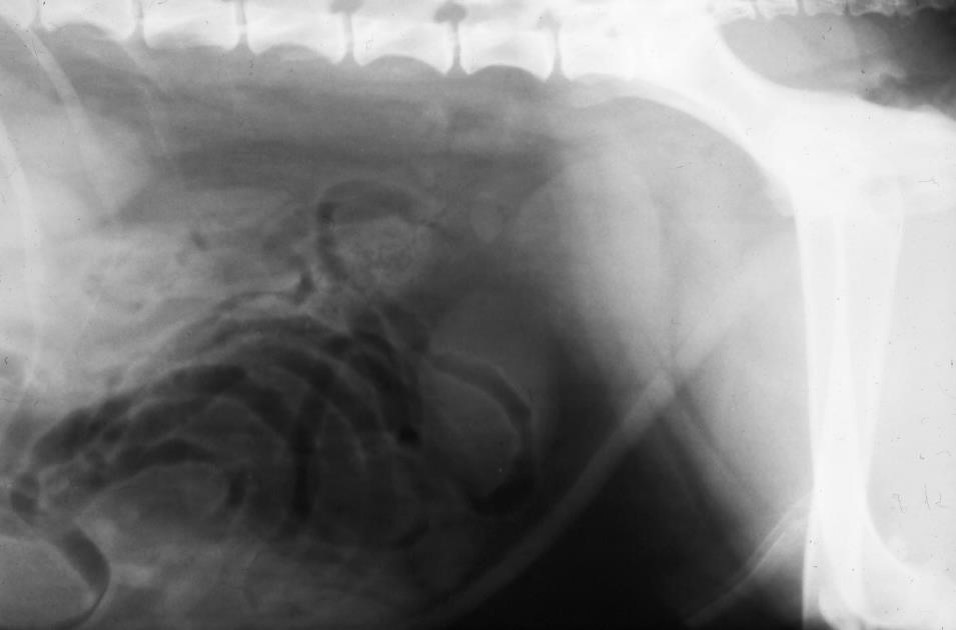

What can be seen here?

Mineral and irregular prostate

New bone around pelvis

Spondylosis of L vert

Which prostatic conditions may be associated with intra prostatic mineralisation? (2)

–Chronic prostatitis

– Neoplasia

New bone on the ventral aspect of caudal vertebrae

Spondylosis

Between end plates – more irregular aggressive new bone

If you get this on caudal vert – pathognomic of neoplasia mets

Marked ST opacity ventralll – LN (infection, or neoplasia)

Local peritoneal dx – increase opacity

Colon – has gas in

Might be LN enlargement near colon

Inflamm vs neoplasia